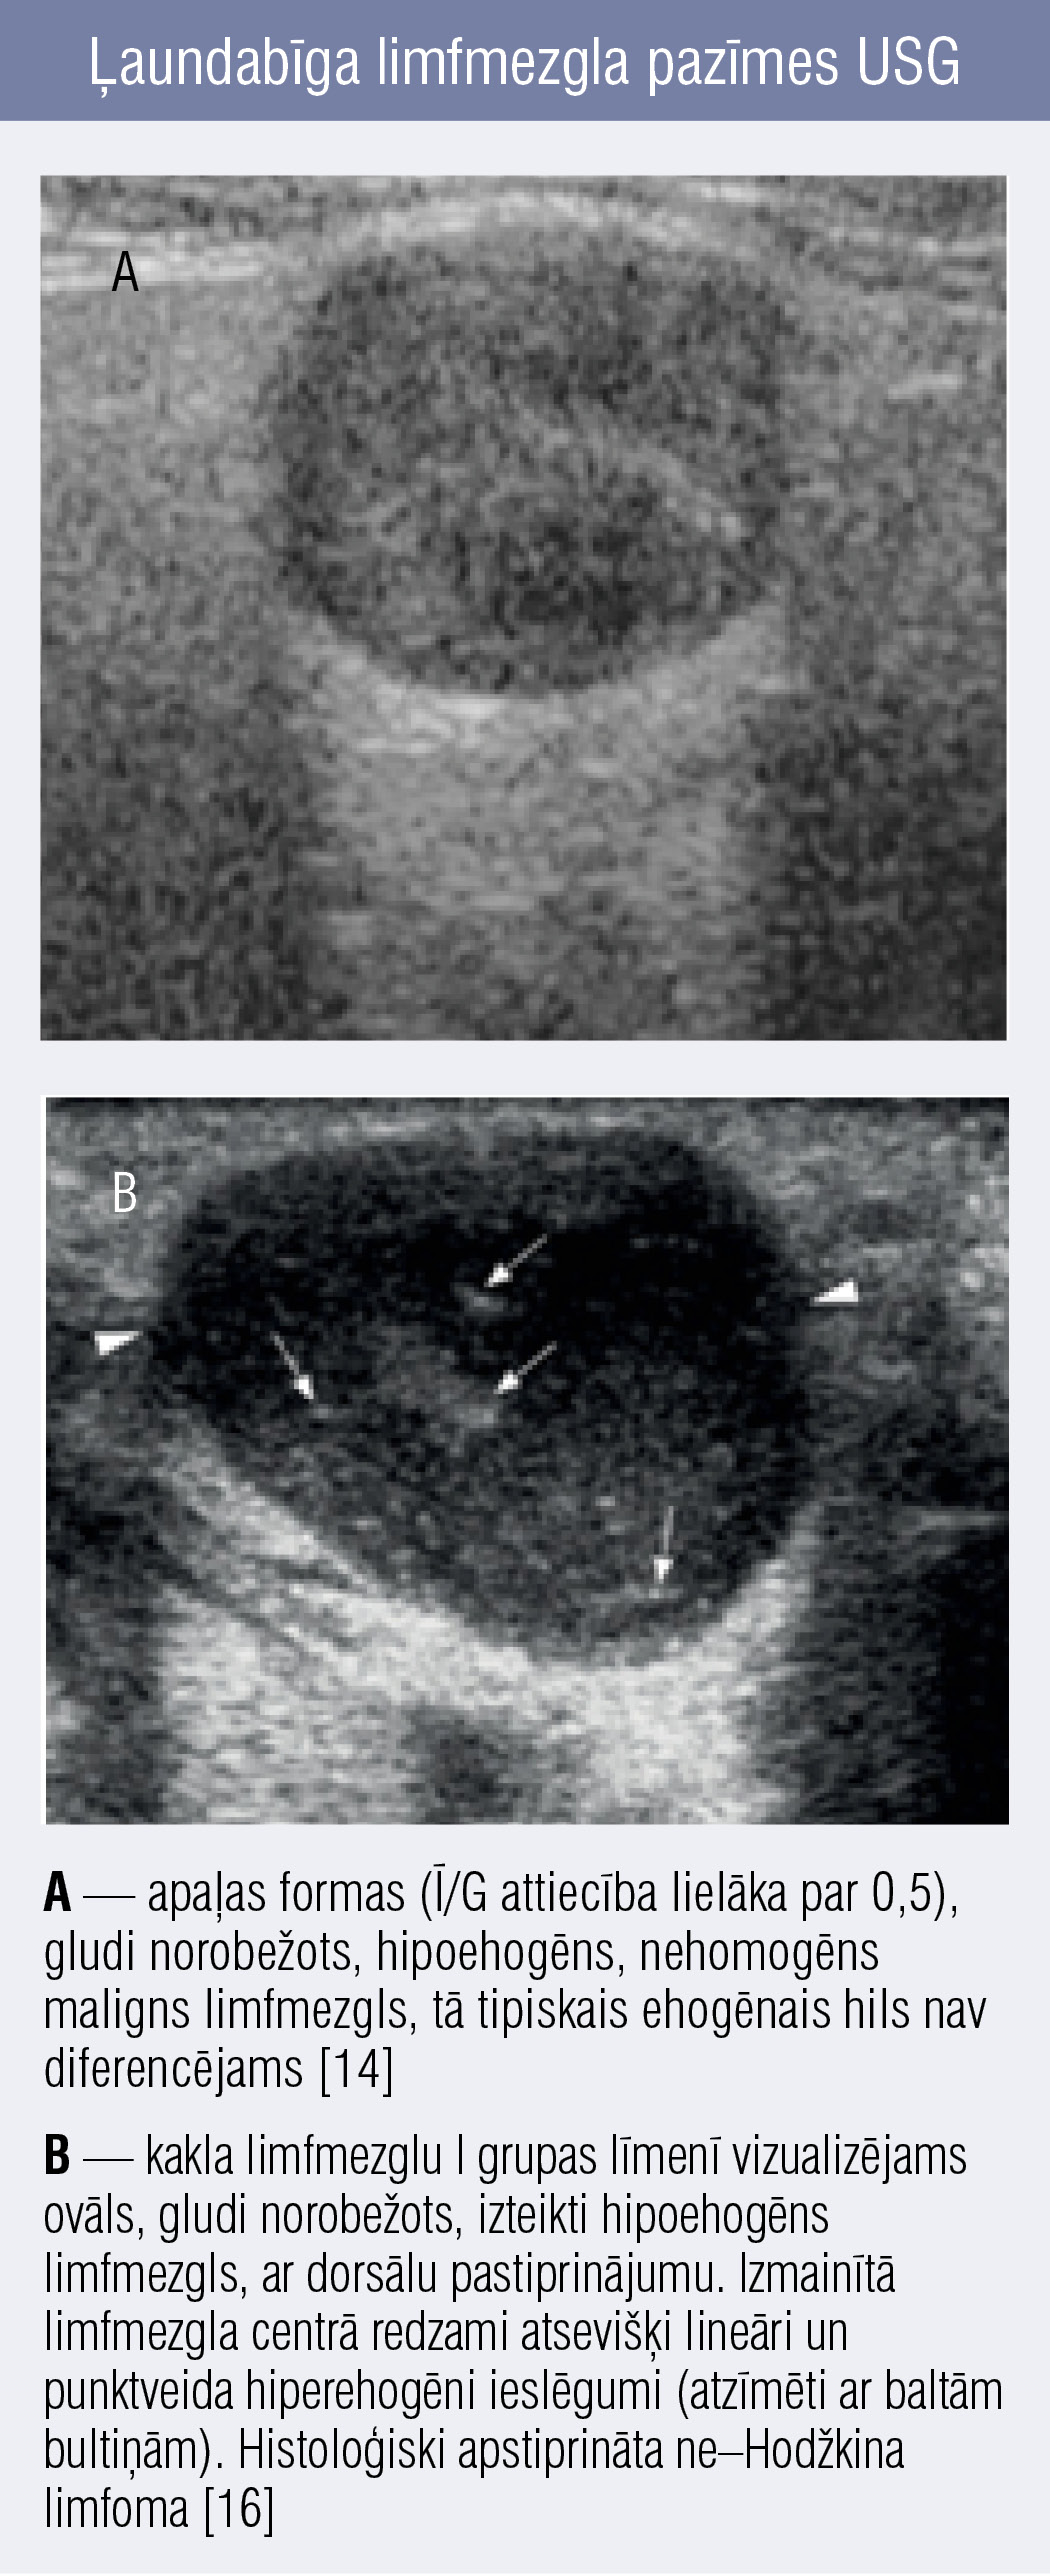

Ļaundabīgi limfmezgli parasti kļūst apaļāki, tāpēc īsās un garās ass attiecība (Ī/G) ir lielāka par 0,5, palīdzot labdabīgus limfmezglus diferencēt no ļaundabīgiem. Tomēr jāatzīmē, ka submandibulārie un parotidālie limfmezgli normāli var būt apaļākas formas ar Ī/G attiecību virs 0,5, tāpēc šo kritēriju šīm lokalizācijām kaklā nevar piemērot konsekventi. [12] Tāpat jāņem vērā, ka infekciozā mononukleoze un citomegalovīruss var izraisīt arī apaļas formas limfadenopātiju. [13]

Malignā procesa infiltrācijas dēļ ļaundabīgi mezgli zaudē ehogēno hilu, bet ~ 4 % gadījumu maligni mezgli var saglabāt ehogēno tauku saknīti, apgrūtinot diagnostiku. [14] Turklāt maligniem limfmezgliem raksturīga jaukta tipa vai perifēra vaskularizācija — atšķirībā no normāla limfmezgla (centrāla tipa vaskularizācija pa neizmainītu tauku saknīti). [15] Līdzīgi kā abscedējošos, arī malignos limfmezglos vizualizēs neregulāras hipoehogēnas vai anehogēnas nekrozes zonas. Taču ap abscedējošiem limfmezgliem iekaisuma procesa dēļ būs redzami paaugstinātas ehogenitātes apkārtējie audi, savukārt maligniem limfmezgliem šāda atrade parasti nav vērojama (8. attēls). [16]

Ļaundabīga limfmezgla pazīmes USG Ļaundabīga limfmezgla pazīmes USG

8. attēls

Ļaundabīga limfmezgla pazīmes USG